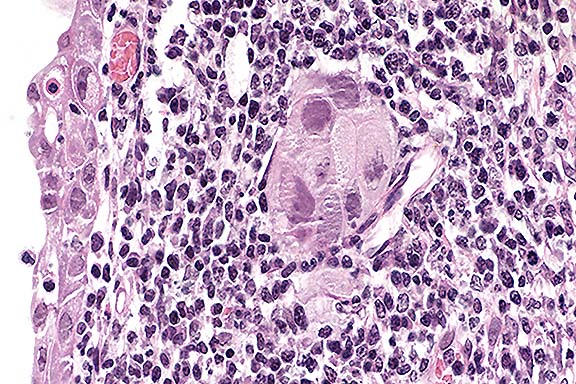

Contributor's Diagnosis and Comments: Rhinitis, subacute, focally extensive, moderate, with intranuclear inclusions and megalocytosis, glandular epithelium of turbinates, consistent with porcine cytomegalovirus (Herpesvirus) aka "inclusion body rhinitis".

Case 18-1. Nasal turbinate. Surface epithelial cells have basophilic nuclear inclusions and are undergoing necrosis. The mucous gland in the center has very hypertrophic cells and nuclei that contain diffuse basophilic inclusions (cytomegalovirus). 40X

AFIP Diagnosis: Nasal turbinates: Rhinitis, necrotizing, subacute, multifocally extensive, moderate, with multifocal squamous metaplasia, glandular cytomegaly and karyomegaly, and basophilic intranuclear inclusion bodies, Yorkshire cross, porcine, etiology consistent with porcine herpesvirus 2.

Conference Note: Inclusion body rhinitis, caused by porcine herpesvirus 2 (porcine cytomegalovirus) is primarily an acute to subacute disease of suckling piglets characterized by mild to severe necrotizing rhinitis with large basophilic intranuclear inclusions in the epithelium of the mucous glands and ducts in the nasal mucosa. In general, morbidity is high and mortality is low. Infection is usually asymptomatic in older animals; however, in naive herds, disease and occasional deaths may be experienced in 4- to 12-week-old pigs. Infection of pregnant sows may result in delivery of small litters, fetal mummification, stillbirths, neonatal deaths, and runt pigs with rhinitis and/or pneumonia. Subsequent decreased conception rates may occur in affected sows.

The large basophilic intranuclear inclusion bodies, when correlated with appropriate signs, are diagnostic for inclusion body rhinitis. However, cytomegaloviruses can also produce typical herpetic inclusions without cytomegaly and as such, pseudorabies would have to be eliminated as a cause, particularly in locations such as lung and CNS. The lesions associated with inclusion body rhinitis with a secondary bacterial infection could mimic the early changes associated with atrophic rhinitis. Advanced atrophic rhinitis, with loss of nasal turbinates, should not be difficult to distinguish from inclusion body rhinitis.